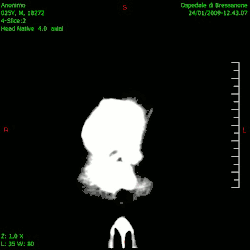

Die Skala ist theoretisch nach oben offen. In der Praxis hat sich der Bereich von −1024 HU bis 3071 HU durchgesetzt; diese 4096 Graustufen können mit einer zwölfstelligen Binärzahl dargestellt werden (212 = 4096). Metalle können jedoch noch stärkere Absorption, bis hin zur Totalabsorption (die sich dann nicht darstellen lässt) bewirken. Da auf der Skala messtechnisch deutlich mehr Schwächungswerte klar getrennt werden als das menschliche Auge auf einer Graustufenskala unterscheiden kann, wird im Bild durch Fensterung immer nur der Teil der Hounsfieldskala eingeblendet, der zu untersuchende Bildinhalte darstellt.